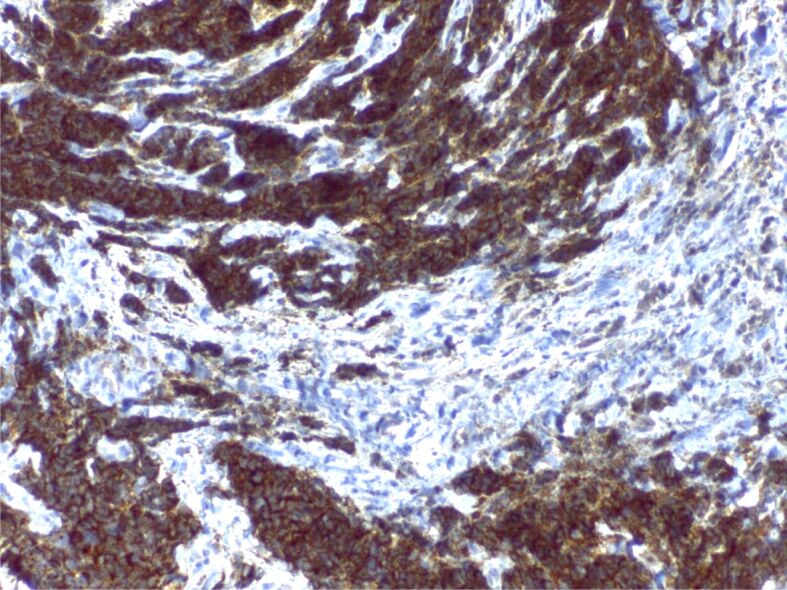

Abstract Image